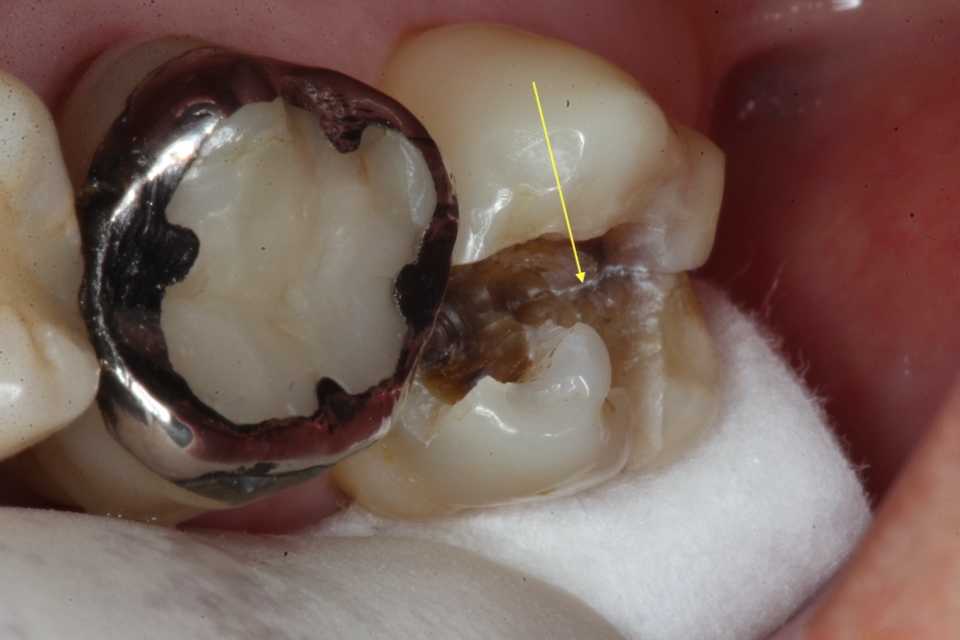

歯茎部カリエス(応力腐食割れ)0.2 2025.08.01

歯茎部カリエス(応力腐食割れ)0.1 2025.07.31

歯茎部カリエス(応力腐食割れ)0.0 2025.07.26